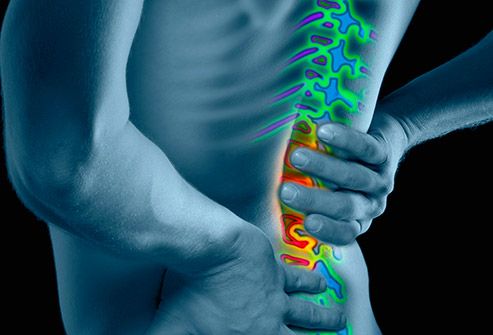

چند راهکار ساده برای رهایی از کمر درد کمردرد یک مشکل آزار دهنده است که بیشتر افراد در برهه ای از زندگی خود آن را تجربه می کنند، اما با چند راهکار ساده مانند ورزش کردن، انجام حرکات کششی و حفظ وزن سالم می توان از بروز این درد پیشگیری کرد.کمردرد می تواند به صورت های مختلف بروز کند و …

5 روش اثباتشده برای خاتمه دادن به کمردرد کمردرد میتواند حدود 80 درصد از ما را در برههای از زندگی تحت تاثیر قرار دهد. کمردرد مهمترین عامل ناتوانی مربوط به شغل است. تحقیقی در سال 2014 در ژورنال Annals of the Rheumatic Diseases منتشر شد که بر اساس نتایج آن کمردرد در مقایسه با دیگر مشکلات سلامتی موجب ناتوانی بیشتری در …